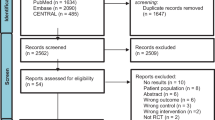

The TEHAF study, a randomised controlled trial performed between 2007 and 2010, compared tailored telemonitoring using the Health Buddy to usual care in HF patients [10]. Further study details have been published elsewhere [7]. In brief, HF patients with New York Heart Association (NYHA) functional class 2–4 that were treated by a cardiologist and were in the care of a heart failure nurse (HFN) were included. HF was defined as ‘at least one episode of fluid retention requiring diuretics, either with an echocardiographic left ventricular ejection fraction ≤40% or a preserved ejection fraction with diastolic dysfunction’ [7]. Patients were included in the study either during a visit to the outpatient clinic of one of the participating centres (Sittard, Heerlen, Maastricht) or when they were visited by a HFN, in the home situation. Exclusion criteria were: unable to give informed consent, visual impairment, hearing impairment in combination with living alone, no command of the Dutch language, planned hospital admission within 3 months and/or chronic obstructive pulmonary disease, Parkinson’s disease, extracorporeal dialysis, (pre)dementia or another disease with an expected shortened lifespan. A total of 382 patients were included. The trial was completed by 301 patients (79%). All patients who did not finish the study were excluded from all further analyses. The follow-up period was 12 months. Before randomisation, written informed consent was obtained. Randomisation was computer-generated with stratification per centre. Four times during the study, data on patients’ self-care behaviour (measured with the European Heart Failure Self-Care Behaviour Scale) [11], self-efficacy (measured with the Barnason Efficacy Expectation Scale) [12] and compliance (measured with the Heart Failure Compliance Scale) [13] were collected (Fig. 1).